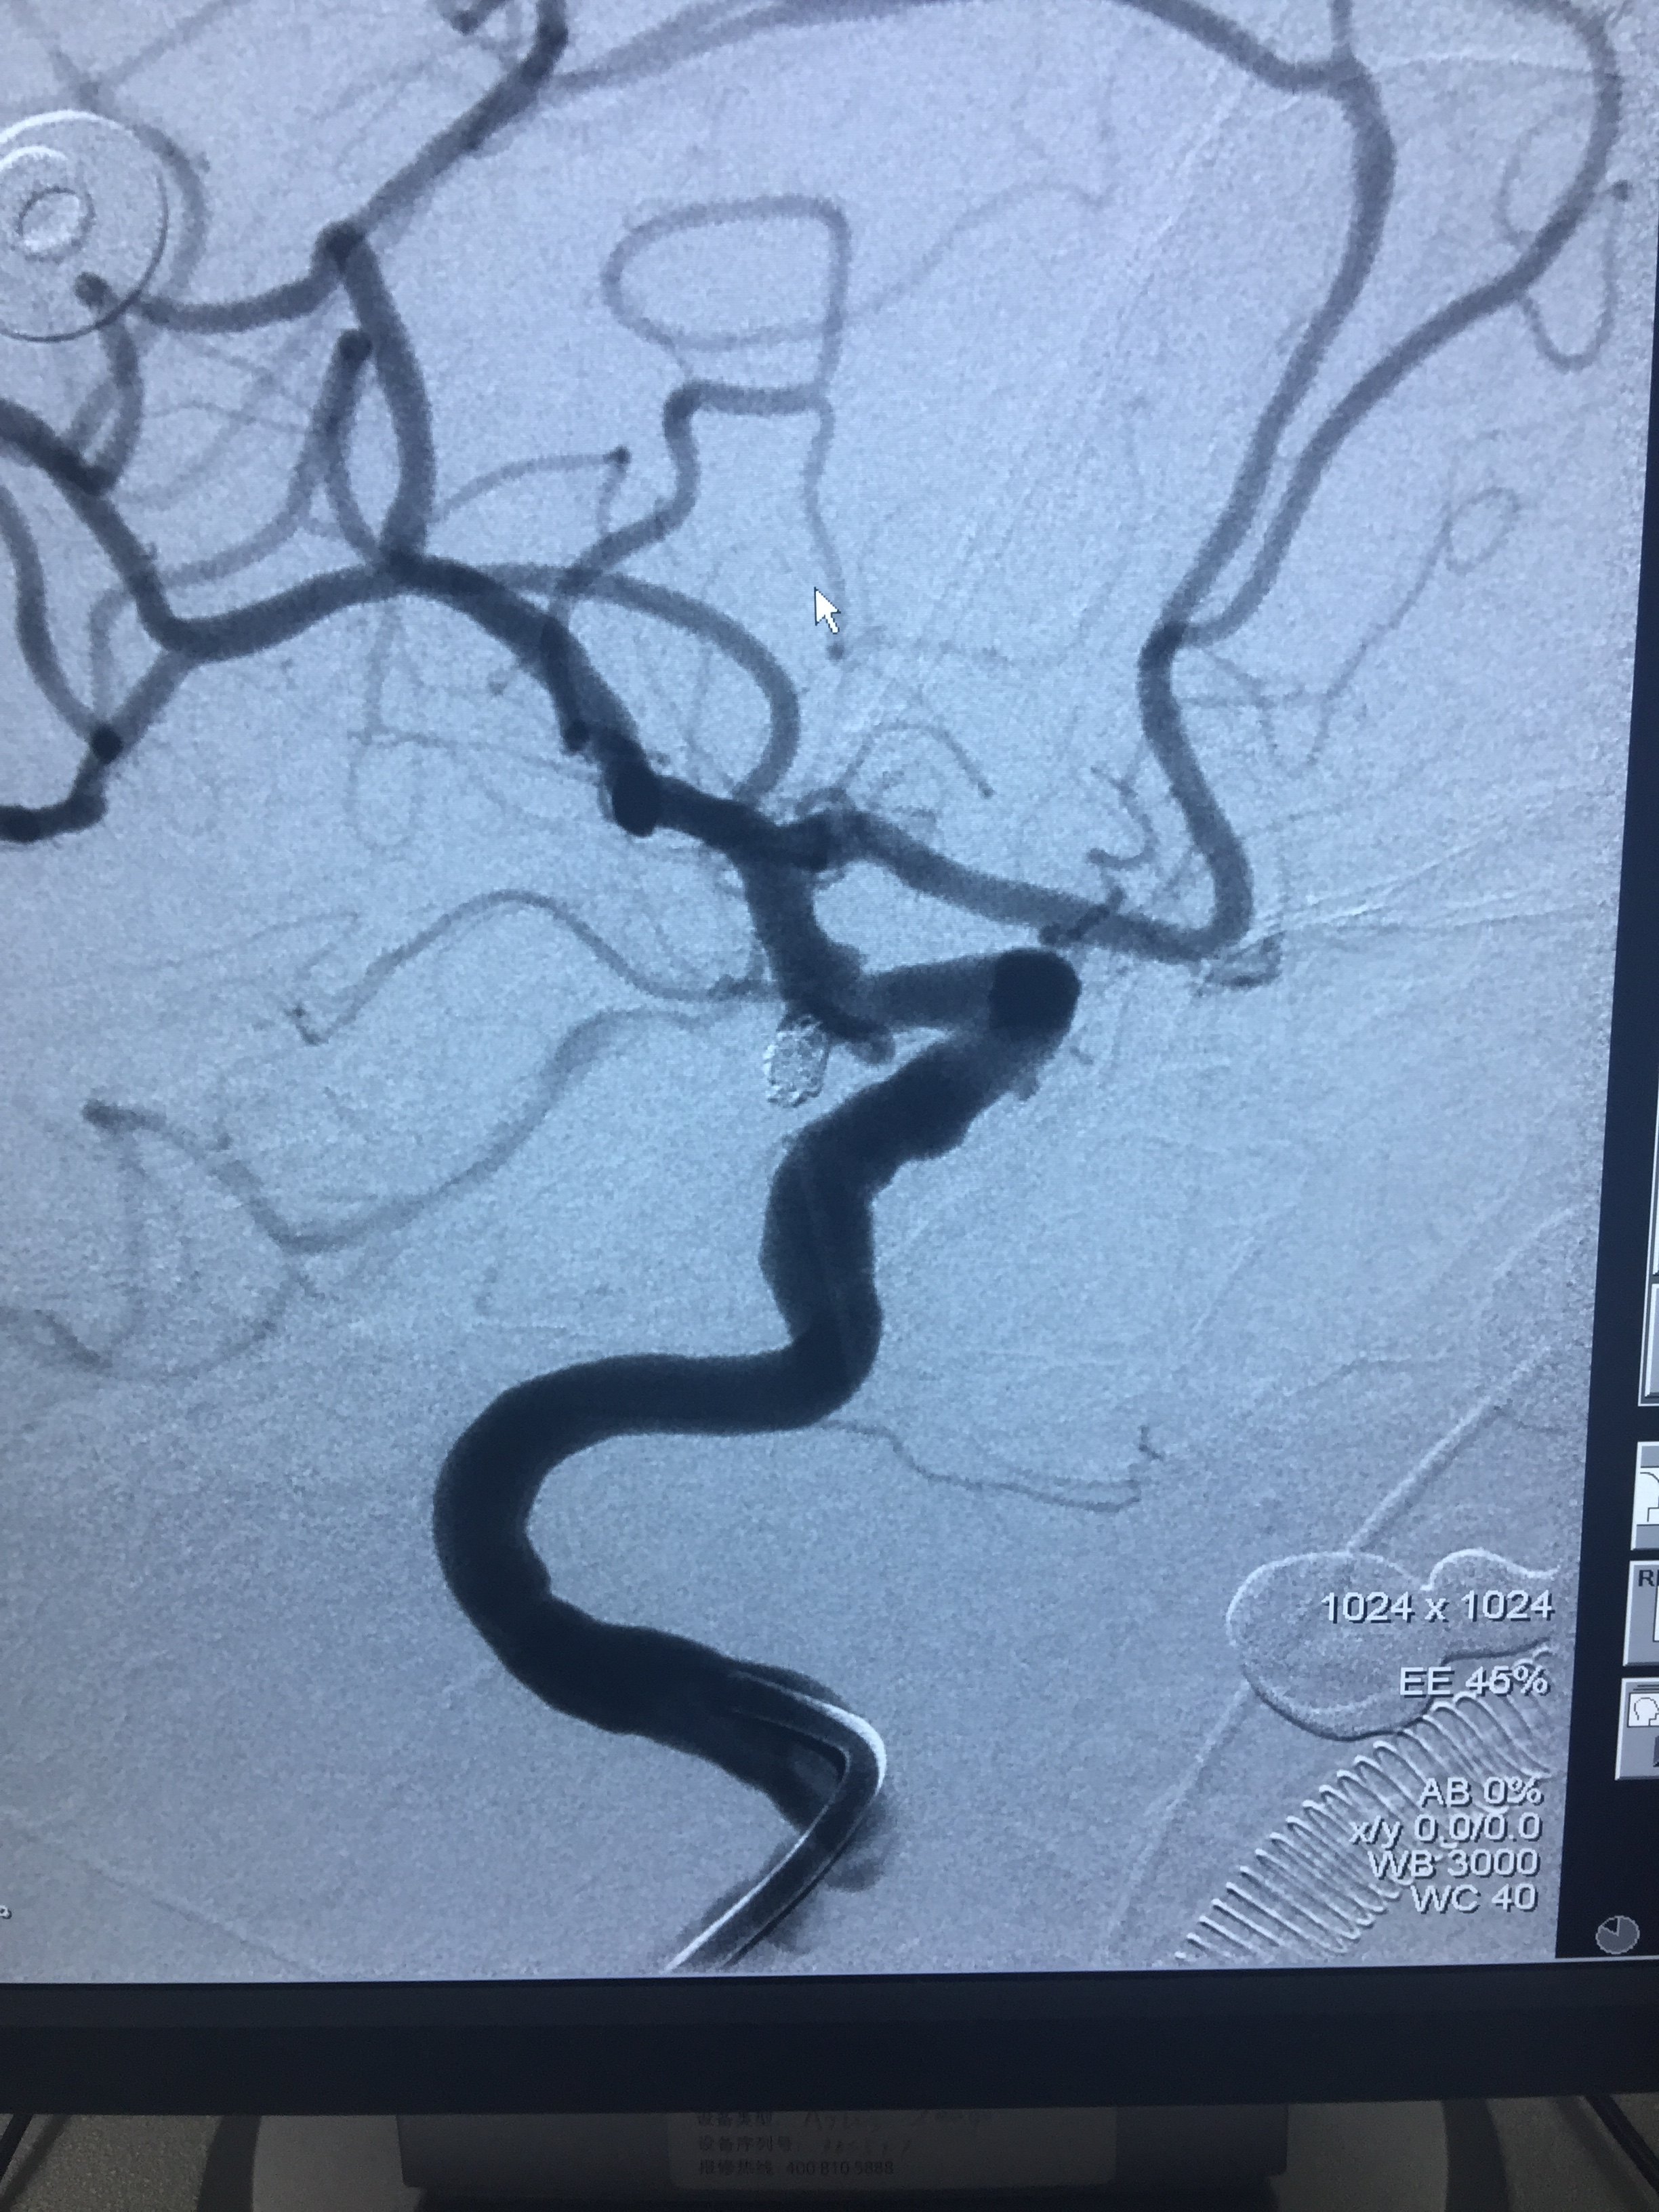

病例三:后交通动脉瘤-术前

1534032343.png